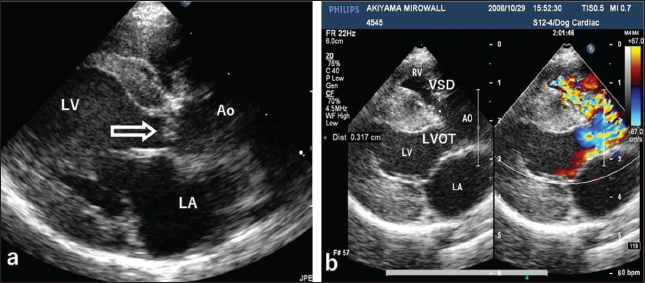

Auscultation revealed a heart rate of 150 beats/minutes and a grade 4/6 systolic murmur in the precordial region near the sternum. Electrocardiography revealed a mean electrical axis of +82º and a mitral P wave in the II, III, and aVF leads. Thoracic radiography showed moderate heart enlargement (vertebral heart score, 10 vertebrae; cardio-thoracic ratio [CTR]: 70%) and increased opacity of the pulmonic field. B-mode echocardiography revealed a small polypoid mass at the dorsal part of the interventricular septum below the aortic valve (Fig. 1a). Two areas of flow acceleration were evident, leading to the mosaic pattern on colour flow Doppler echocardiography: one due to a membranous VSD of 3.17 mm in diameter and the other due to LVOT obstruction caused by the mass (Fig. 1b). In the continuous-wave Doppler (CWD) mode, the LVOT blood flow velocity was 4.55 m/seconds, with a calculated systolic pressure gradient (ΔP) of 83 mmHg between the left ventricle (LV) and aorta (Fig. 2a), and the VSD blood flow velocity was 4.55 m/seconds, with a calculated systolic ΔP of 83 mmHg between the LV and right ventricle (RV) (Fig. 2b). Aortic regurgitation (AR) (Fig. 2a) was also observed. In the CWD mode, the AR blood flow velocity was 3.11 m/seconds, with a calculated diastolic ΔP of 39 of mmHg between the aorta and LV (Fig. 2a).

Fig. 1. Echocardiography of the right parasternal long-axis view. (a) B-mode echocardiography shows a small polypoid mass (arrow) at the top of the interventricular septum below the aortic valve. (b) Color Doppler echocardiography of the same view shows two mosaic flows during systole due to a membranous ventricular septal defect (VSD, 3.17 mm in diameter) at the top of the ventricular septum and obstruction of the left ventricular outflow tract (LVOT), respectively. LV: left ventricle, AO: aorta, LA: left atrium, RV: right ventricle.

Echocardiography is the best tool for the detection of intracardiac tumour, especially obstructive myxomas (Bright et al., 1990; Ori et al., 1994; Fernandez-del Palacio et al., 2011; Šimundić et al., 2019; Stack et al., 2021; Mellish et al., 2022). In the present case, auscultation, electrocardiography, and thoracic radiography were also useful. B-mode, colour (Fig. 1a, b), and CWD (Fig. 2a, b) echocardiography clearly revealed a small polyploid mass that moderately obstructed the LVOT, as well as AR and a membranous VSD. The VSD likely caused the AR.